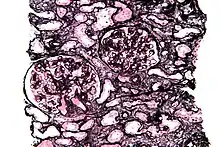

Micrograph of a kidney biopsy stained with a Jones stain.

Jones' stain, also Jones stain, is a methenamine silver-Periodic acid-Schiff stain used in pathology.[1] It is also referred to as methenamine PAS which is commonly abbreviated MPAS.

It stains for basement membrane and is widely used in the investigation of medical kidney diseases.

The Jones stain demonstrates the spiked GBM, caused by subepithelial deposits, seen in membranous nephropathy.